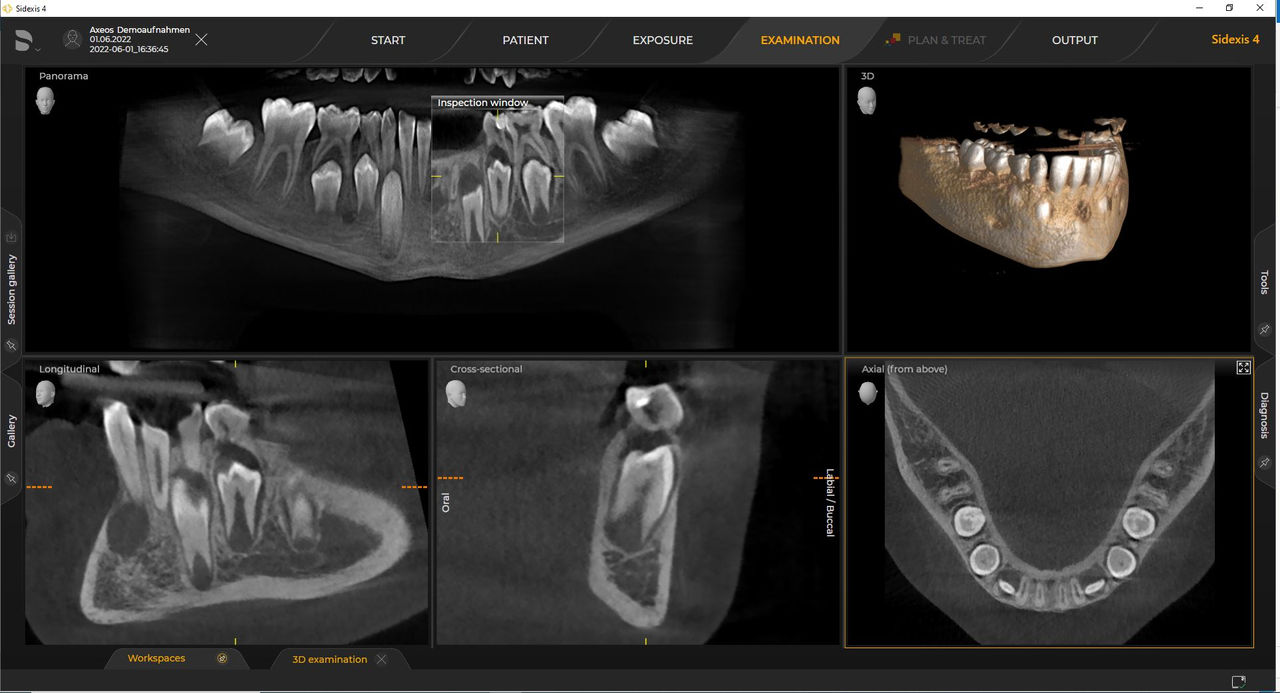

Las unidades 3D de Dentsply Sirona funcionan exclusivamente con Sidexis 4. Sin embargo, la migración de datos de Sidexis XG a Sidexis 4 es muy fácil. Sidexis 4 permite una experiencia digital completa con las últimas herramientas.